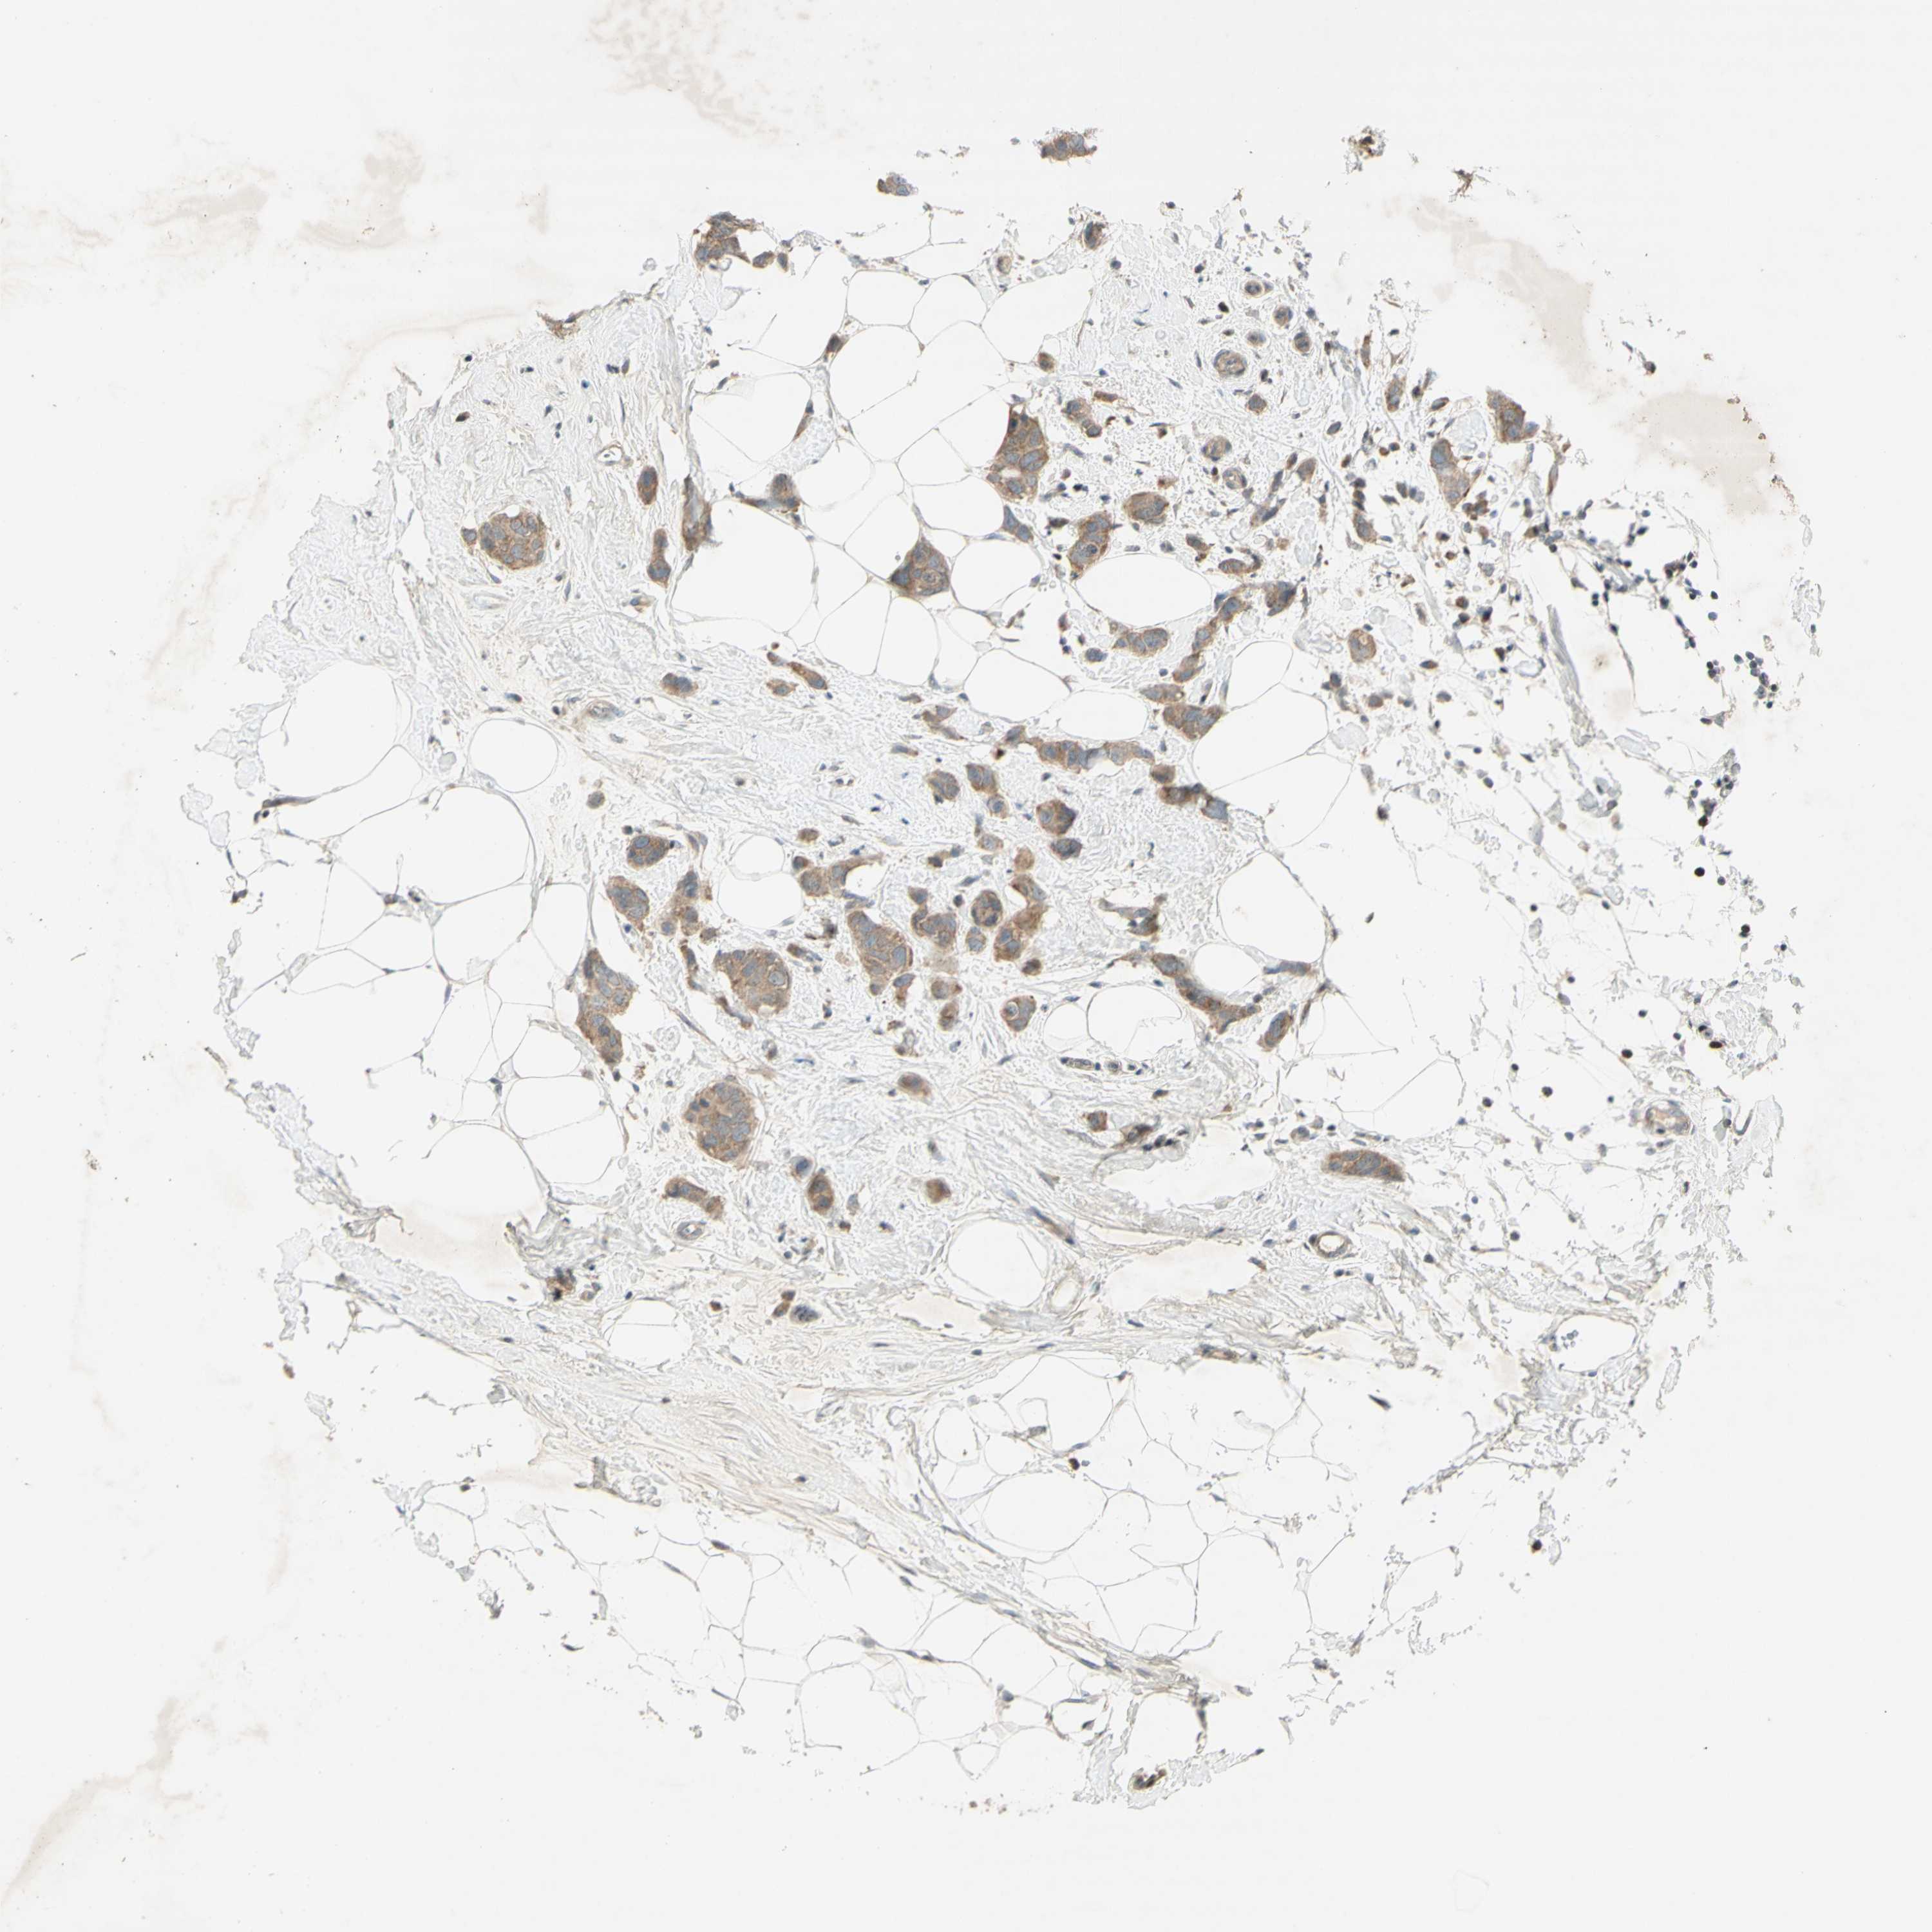

BRCA TCGA BRCA VALIDATION PROTEIN EXPRESSION